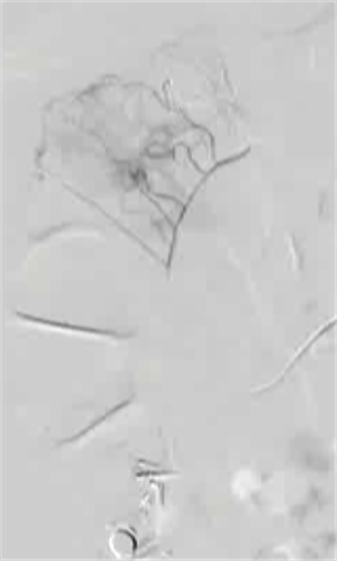

病例1 70/40 mmHg

病例1 20μg Arterenol (去甲肾上腺素) 155/85mmHg

|

激发下 |

栓塞后 |

病例二

100/50 mmHg

20 μց Arterenol 170/80 mmHg

病例3 80/50 mmHg

40 μg Arterenol 170/90mmHg

出血点, |

PVA栓塞 |